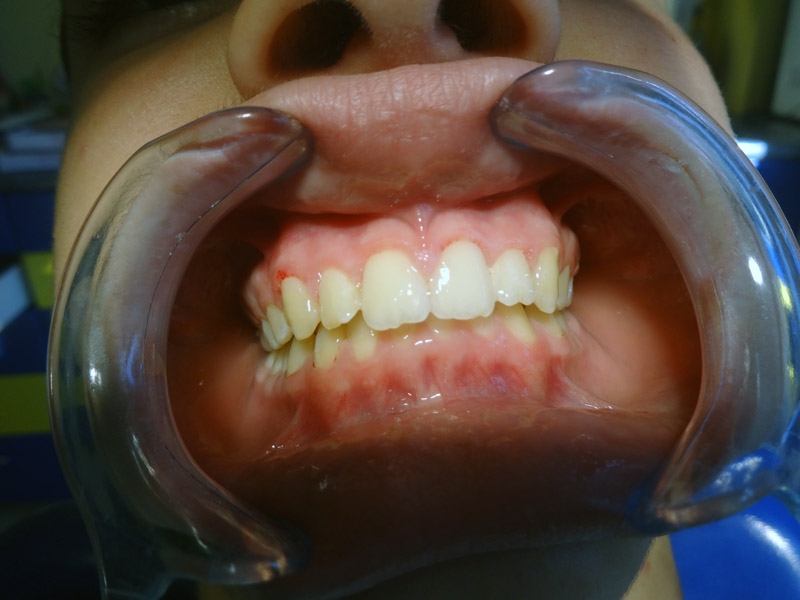

Gingivitis

Gingivitis is caused to the bacterial dental plaque. The main problems related to gingivitis are bleeding from the gums (during tooth brushing), halitosis and swelling of the gums.

Except for the bad oral hygiene, gingivitis is related to hormonal changes during puberty or pregnancy, or the presence of orthodontic mechanisms in the mouth that make difficult to maintain good oral hygiene.